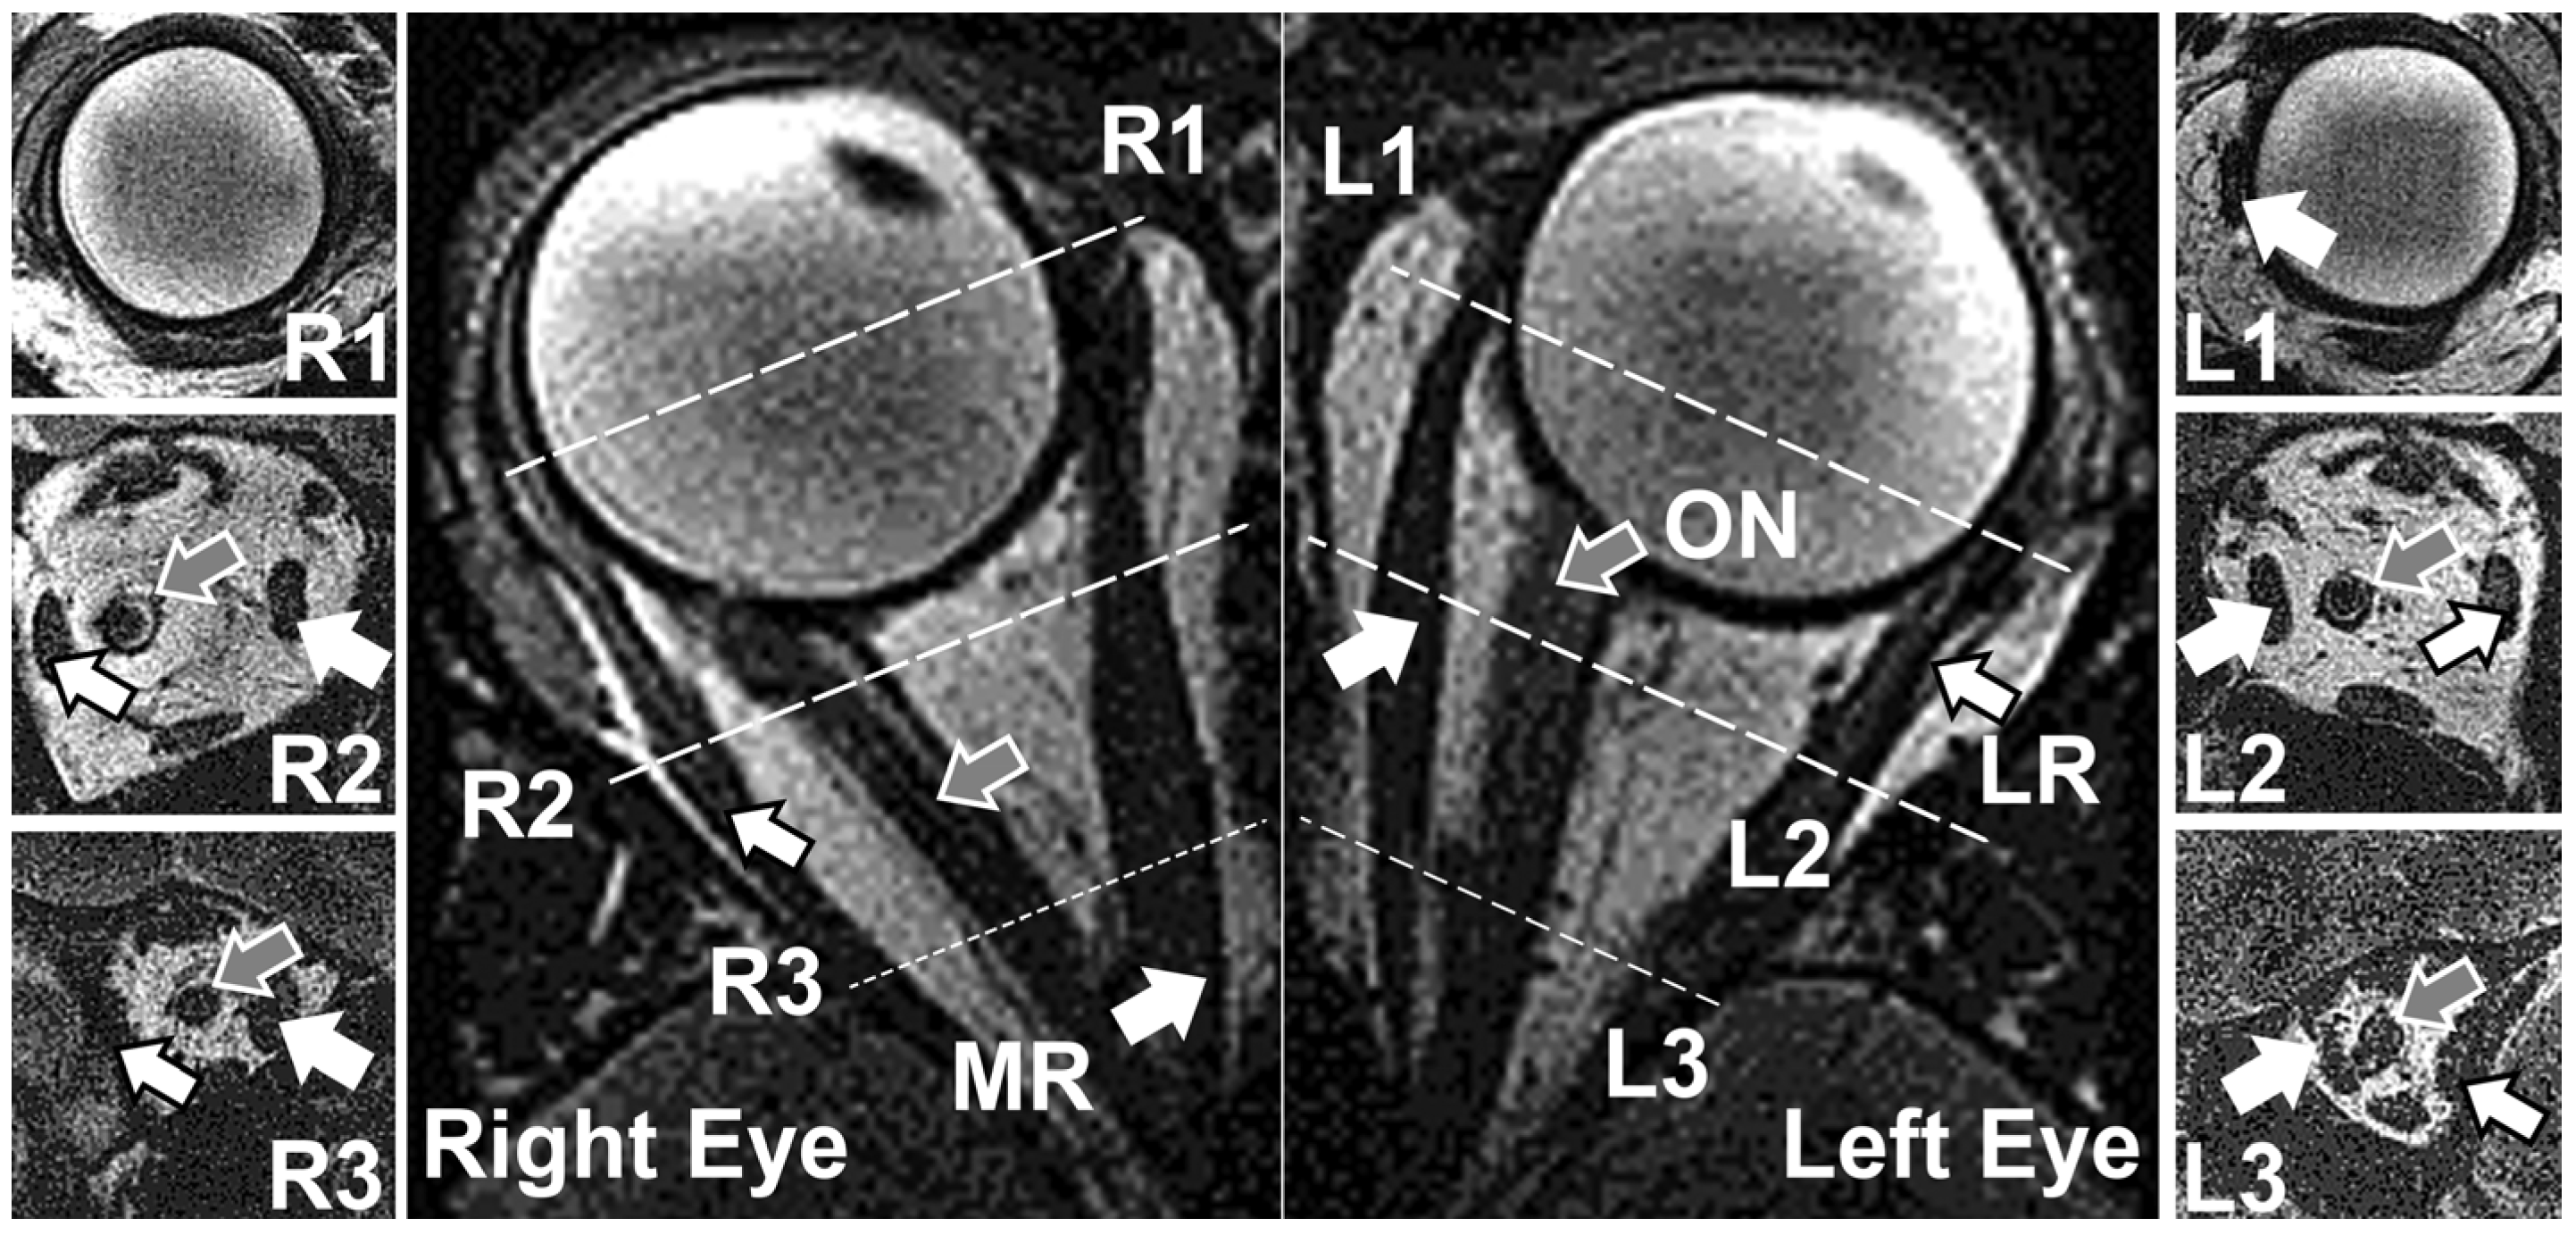

2.2. 3D Reconstruction and Point-Set Registration

2.3. Curve Parametrization

2.6. Local Coordinate Systems for the ON and the Reconstruction of the ON

3.1. Changes in Geometry Due to Eye Rotation